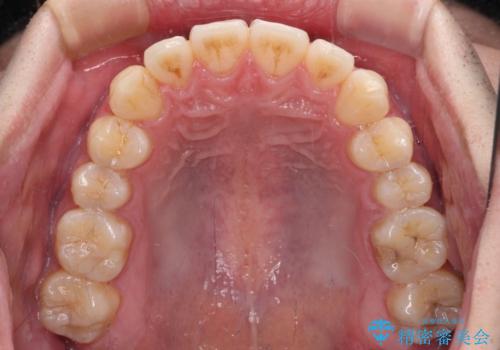

八重歯と前歯のクロスバイト ワイヤー装置で短期間矯正

治療開始の頃は、食事や歯磨きが慣れず、装置が頻繁に脱落しましたが、2,3ヶ月ほどで慣れ、その後は1年ほどで治療を終えることができました。